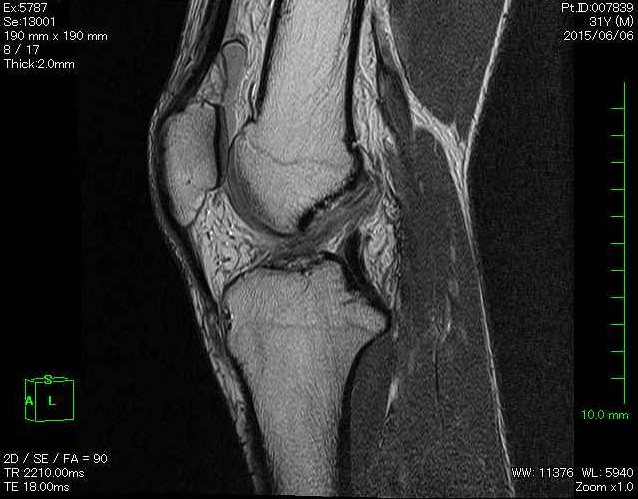

MRIで見る前十字靭帯損傷(イメージ)

正常な前十字靭帯は、MRIで一本のはっきりした白い(または黒い)線として写ります。

損傷している場合、そのラインが途中で途切れていたり、ぼやけていたり、不自然な方向に走って見えることがあります。

画像だけで確定するわけではありませんが、「強い疑い」を裏付ける材料になります。